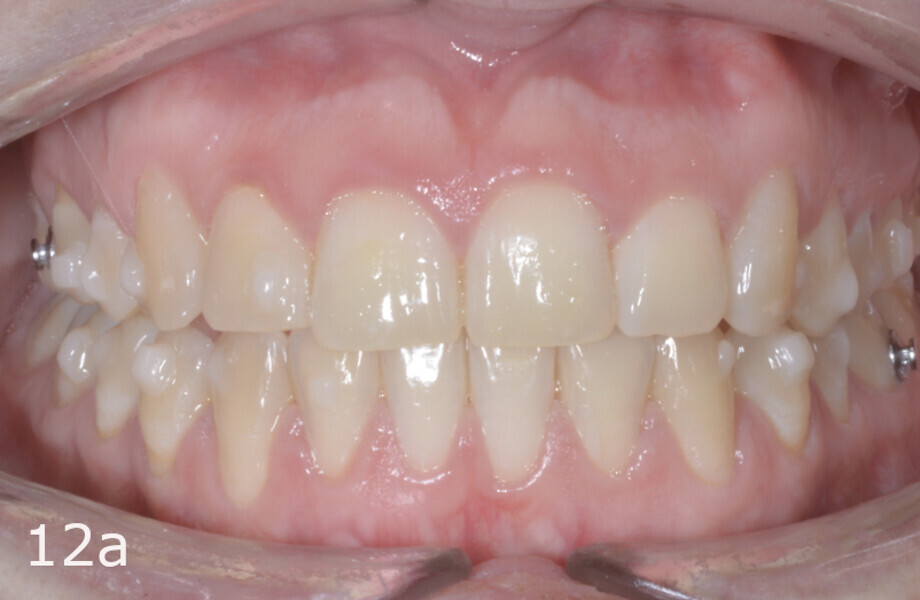

The treatment objectives included closing the anterior open bite, achieving a bilateral Angle Class I relationship and a proper overjet and overbite, correcting the midline discrepancies, and achieving a profile harmonisation. The treatment plan consisted of orthodontic camouflage treatment with asymmetric distalisation in three of the four quadrants using Invisalign aligners (Align Technology) and third molar extraction. The Invisalign Comprehensive package was chosen, and 63 pairs of aligners were used (Figs. 7–10). Each aligner was worn for 20 hours a day for one week each. The use of Class III elastics on both sides was indicated. Afterwards, ten refinement aligners were needed to improve the interdigitation on the right side (Figs. 11 & 12).

Although Class III elastics tend to extrude the maxillary molars and generate clockwise mandibular rotation, aligners allow us to prevent these complications, since we have better control over tooth movement, enabling us to counteract unwanted dental movements. In this case, an intrusion of the posterior teeth was planned, which would generate anticlockwise rotation of the mandible in an anticlockwise direction. This vertical control led to the closure of the anterior open bite and the reduction of the lower facial height, thereby improving the facial profile.